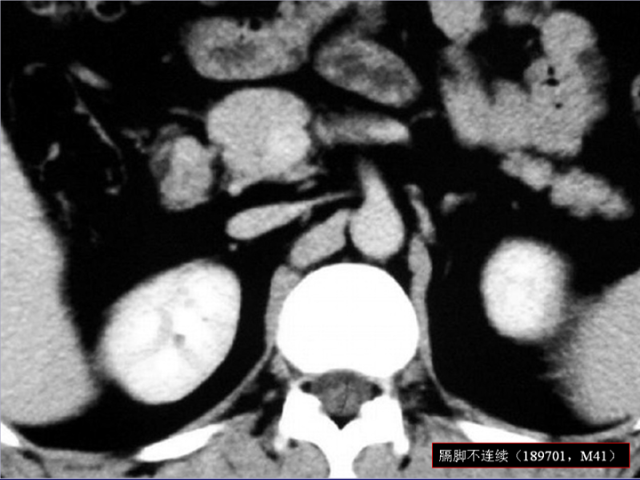

膈肌角解剖及常见变异

作者:王俭 上海长征医院